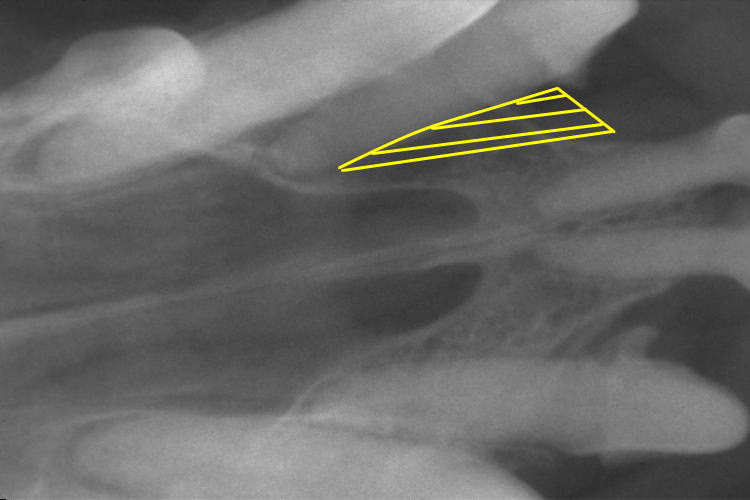

歯科レントゲン

上顎切歯のレントゲンです。

ぐらつきのあった右上顎第3切歯の歯槽骨が吸収し、黒く抜けているのが確認できます。

(黄色斜線部分の歯槽骨が溶けてなくなってしまっています。)